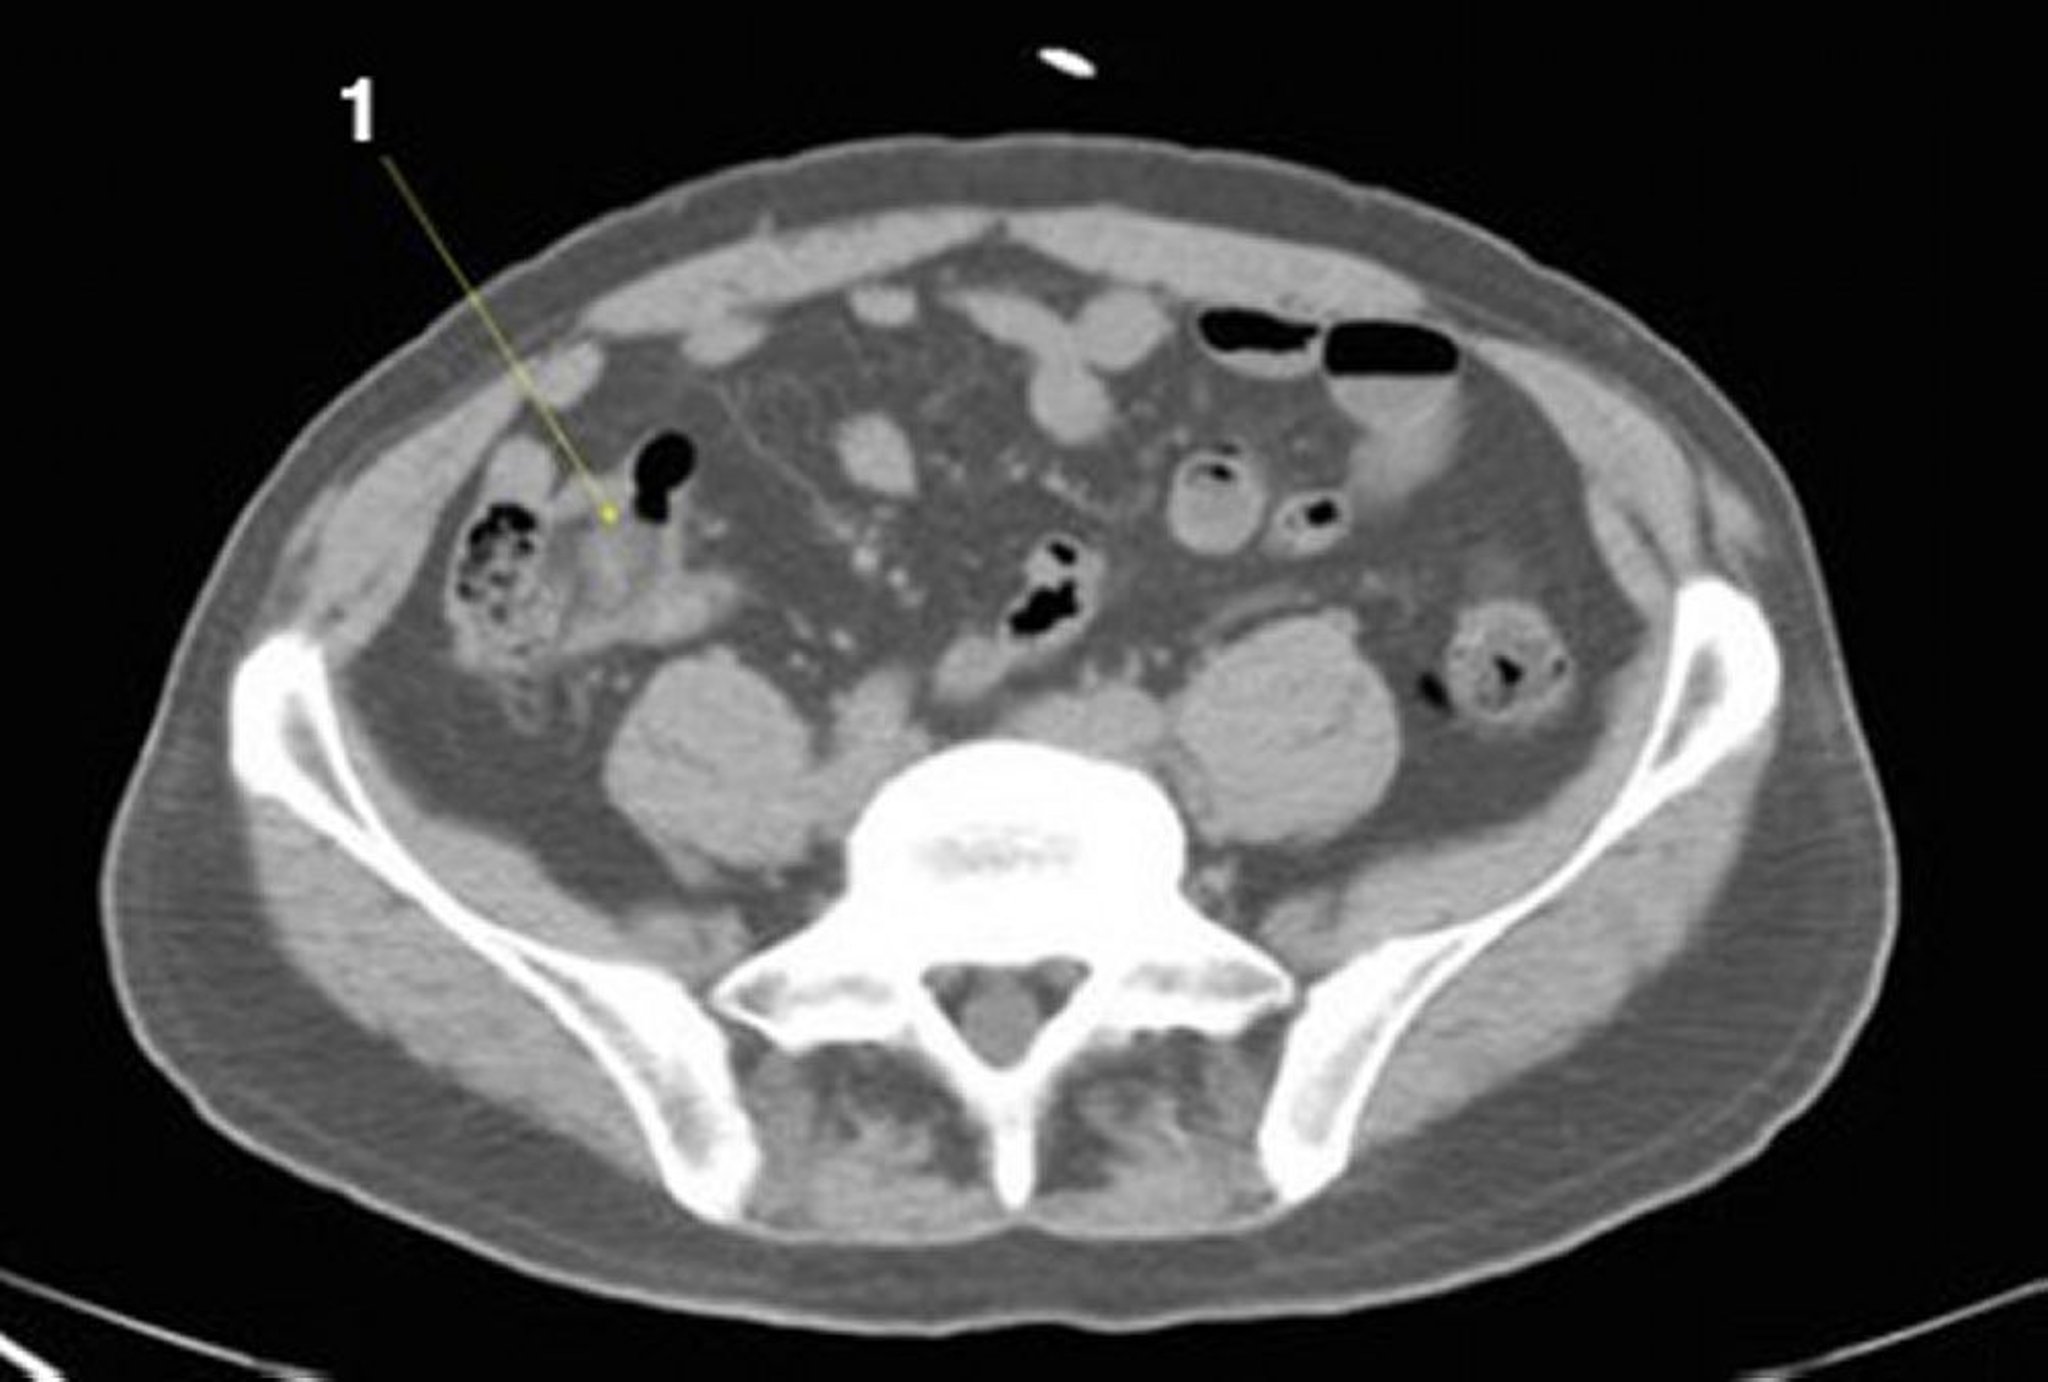

CT-Scan von Abdomen und Becken mit normaler Anatomie ohne Kontrastmittel (Folie 21)

1 = Ileum.